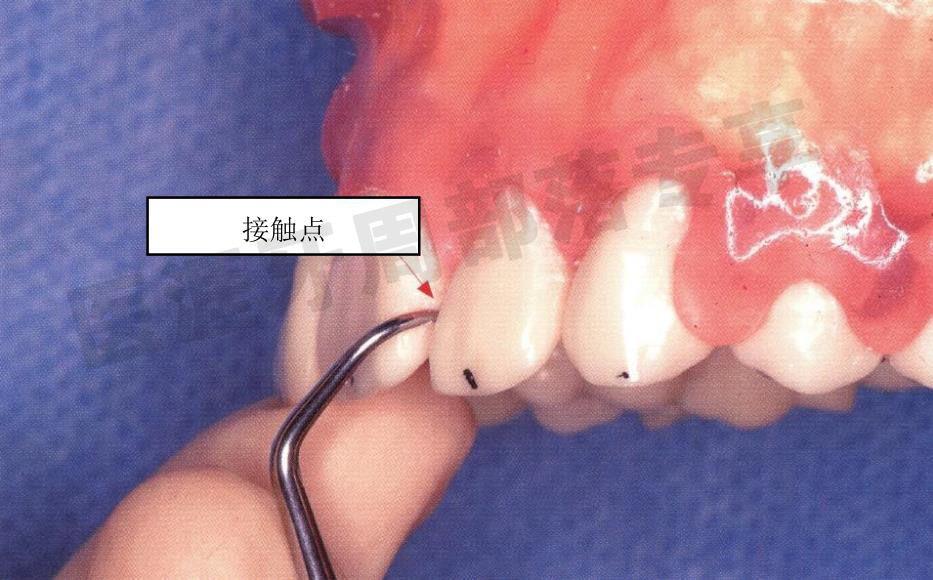

刃部放置于牙冠的接触点上,沿着接触点缓慢插入

怎么选洁牙器械5个要点带你学习器械洁牙_https://www.jmylbn.com_新闻资讯_第20张

怎么选洁牙器械5个要点带你学习器械洁牙_https://www.jmylbn.com_新闻资讯_第21张